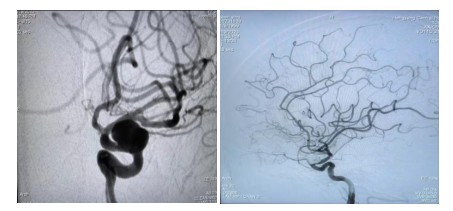

原來64歲的羅奶奶因為發(fā)現(xiàn)頸動脈瘤10余天,來到衡陽市中心醫(yī)院全科醫(yī)學(xué)科住院,在完善腦血管造影檢查后,診斷其為左側(cè)頸內(nèi)動脈眼動脈段動脈瘤,瘤體大,并有分葉子瘤,為高危破裂動脈瘤。危急之下,轉(zhuǎn)入神經(jīng)內(nèi)科一病區(qū)準備進行介入手術(shù)治療。

經(jīng)過充分的術(shù)前準備工作,神經(jīng)內(nèi)科中心主任丁菁帶領(lǐng)介入團隊與導(dǎo)管室、麻醉科等多學(xué)科共同協(xié)作,順利為羅奶奶實施了血流導(dǎo)向密網(wǎng)支架輔助下顱內(nèi)動脈瘤栓塞術(shù)。手術(shù)過程順利,術(shù)后羅奶奶在麻醉蘇醒后安返病房。在神經(jīng)內(nèi)科一病區(qū)醫(yī)護人員的精心護理下羅奶奶恢復(fù)良好,順利出院。

介入治療動脈瘤,是目前國內(nèi)外大中心治療動脈瘤的主要方法。最常見是把動脈瘤腔用微彈簧圈進行填塞,使瘤腔內(nèi)形成血栓達到動脈瘤的致密栓塞、解剖治愈的目的。對于有一些大的動脈瘤瘤頸非常寬,栓塞后仍有很高的復(fù)發(fā)率??梢圆捎醚鲗?dǎo)向裝置,也就是密網(wǎng)支架治療動脈瘤。它是最新的治療方法,我們的羅奶奶就是采用這種治療方法。

密網(wǎng)支架又被稱為血流導(dǎo)向裝置,是一種新型的介入栓塞材料。它在血管內(nèi)跨過動脈瘤釋放支架。由于這個支架的網(wǎng)眼非常小,導(dǎo)絲非常細,會干擾并減少從載瘤動脈進入動脈瘤的血流,使動脈瘤中血流出現(xiàn)阻滯,導(dǎo)致動脈瘤內(nèi)血栓形成,表現(xiàn)為“血流導(dǎo)向”作用;同時它提供血管內(nèi)皮細胞攀爬生長的腳手架,促進內(nèi)皮化修復(fù)。它較彈簧圈栓塞操作更簡便,手術(shù)風(fēng)險降低,更安全。